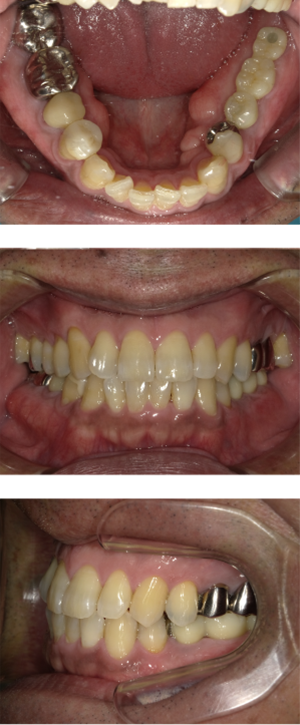

50代 インプラント治療(右上3左上3のみGBR)

| 年代・性別 | 50代・男性 |

| 主訴 | 入れ歯が合わず毎日ヨーグルトしか食べることができないので、しっかり咬めるインプラントにしたい。 |

| 部位 | 右下⑦⑥5④ 上顎③2①①2③ 左下67 |

| 治療期間 | 約9ヶ月 |

| 費用 | ¥4,273,500(税込) |